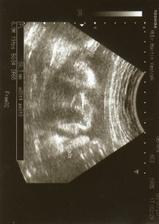

Naše první očekávané miminko

Děkujeme teto.5.ledna jdem na další.Už se těším až ho zase uvidím.

Ahoj beru, krásnej prďolka, tak přidávej fotečky, těším se....